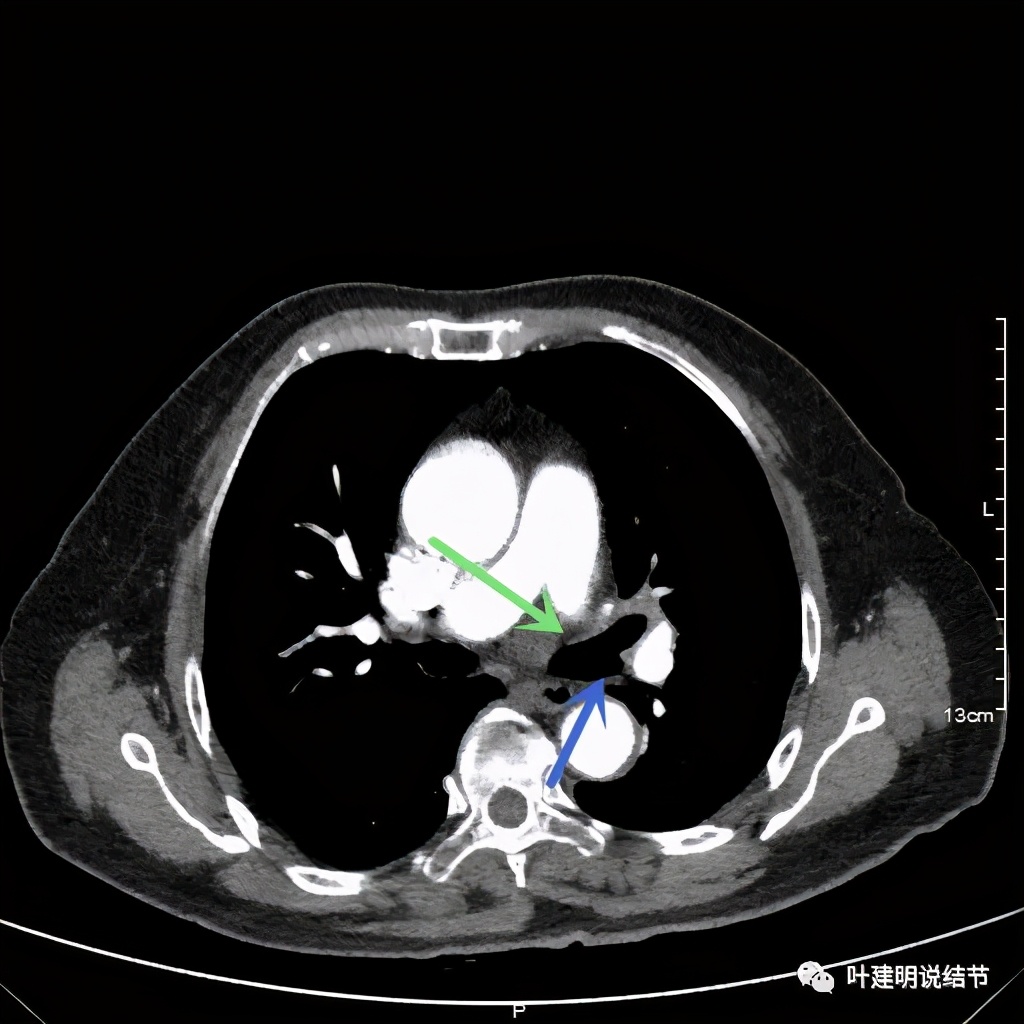

左上肺基本已经不见肿瘤,只在主动脉旁少许软组织影

上图示主动脉弓水平仍见软组织影

上图桔色箭头示左肺动脉分支处仍被软组织(原肿瘤所在)包绕,粉色箭头示肺动脉仍与肿瘤处关系密切

上图也示桔色箭头示左肺动脉分支处仍被软组织(原肿瘤所在)包绕,粉色箭头示肺动脉仍与肿瘤处关系密切

上图绿色示左上叶支气管,蓝色示下叶支气管开口处